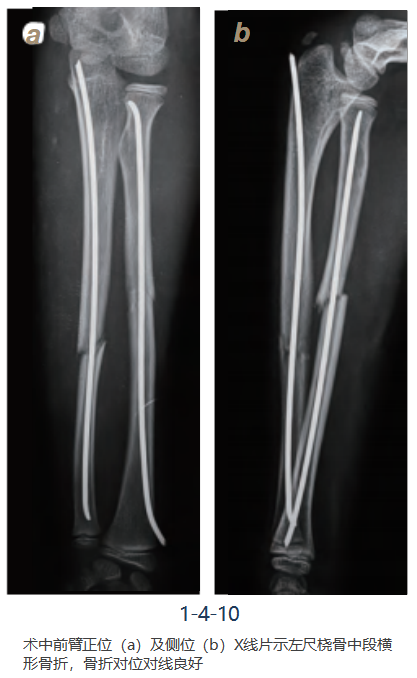

9. 关闭切口:

剪断弹性钉钉尾,保留皮质外约1cm,逐层关闭切口并确认前臂旋 转及腕关节屈伸活动良好。术中前臂正侧位X线片确认骨折复位及内固定位置(图1-4-10)。